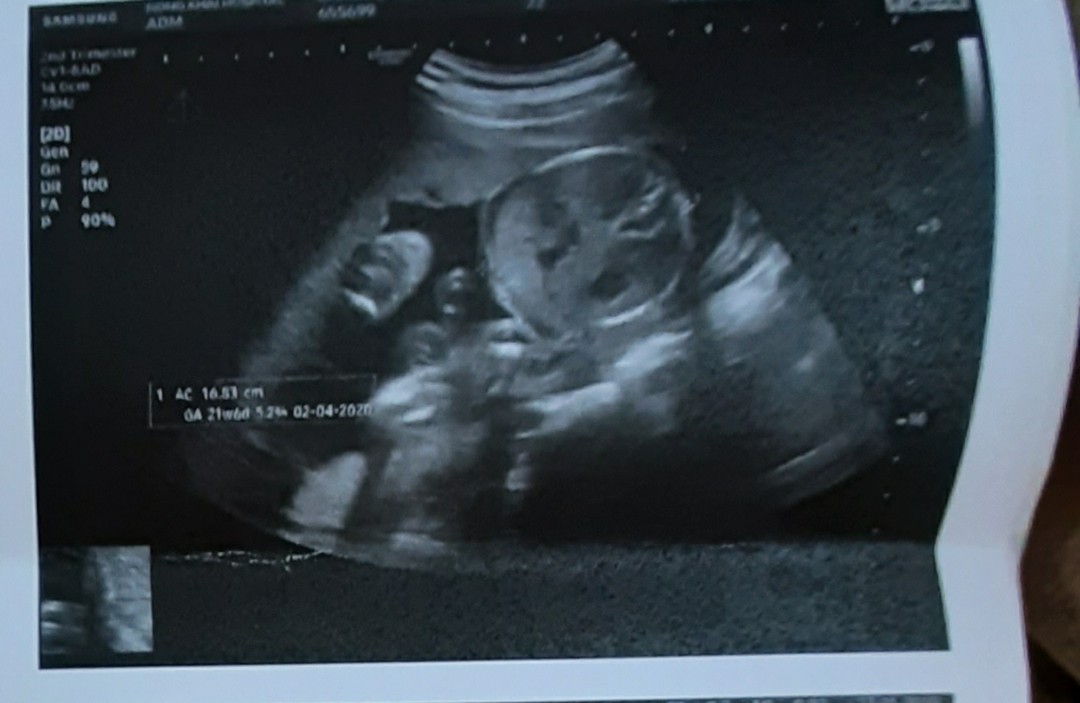

พึ่งซาวด์วันนี้ค่ะ อยากได้ผช. ได้สมใจ ?❤️?